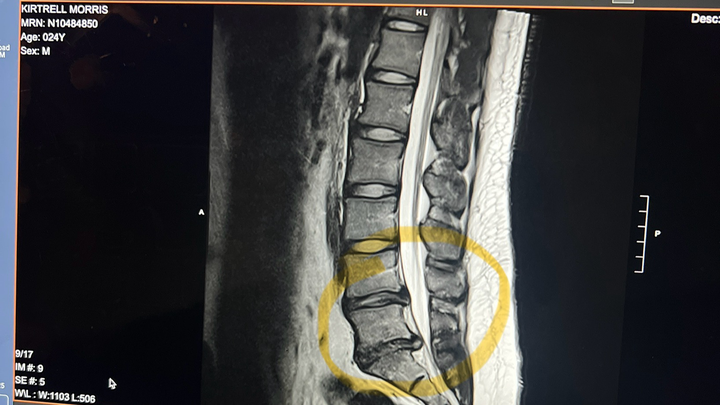

Recently, I was diagnosed with two herniated discs (L4-L5 and L5-S1) that were pressing on my sciatic nerve, causing severe pain and making it impossible to walk, stand, or lift, which are all essential parts of my work. On October 22, 2025, after having tried everything PT, Steroid Injections, Occupational Therapy and more desperately wanting to gain normalcy in my life again, I underwent a micro-discectomy (a minimally invasive surgery to relieve pressure on a spinal nerve caused by a herniated disc) to relieve the pressure on my nerves and begin my road to recovery.